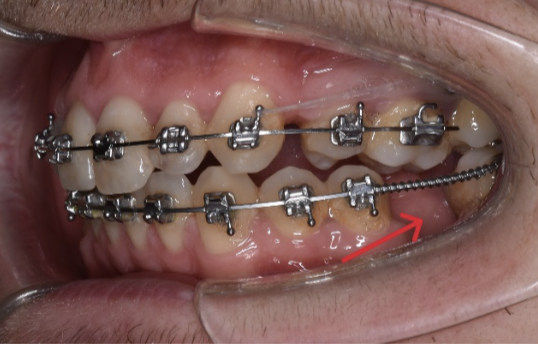

Aici avem un caz in care inghesuirea dentare grava s-a rezolvat prin tratament orthodontic cu extractii dentare.

Se poate observa ca nu exista spatiu pentru eruptia caninilor.

S-a realizat extractia a 2 premolari:

Iar acesta este aspectul final: